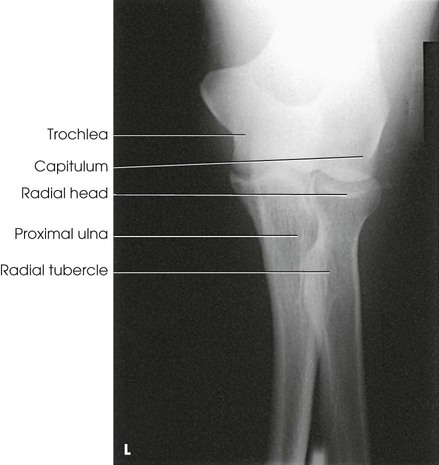

Structures shown

An AP projection of the elbow joint, distal arm, and proximal forearm is presented (Fig. 4-111).